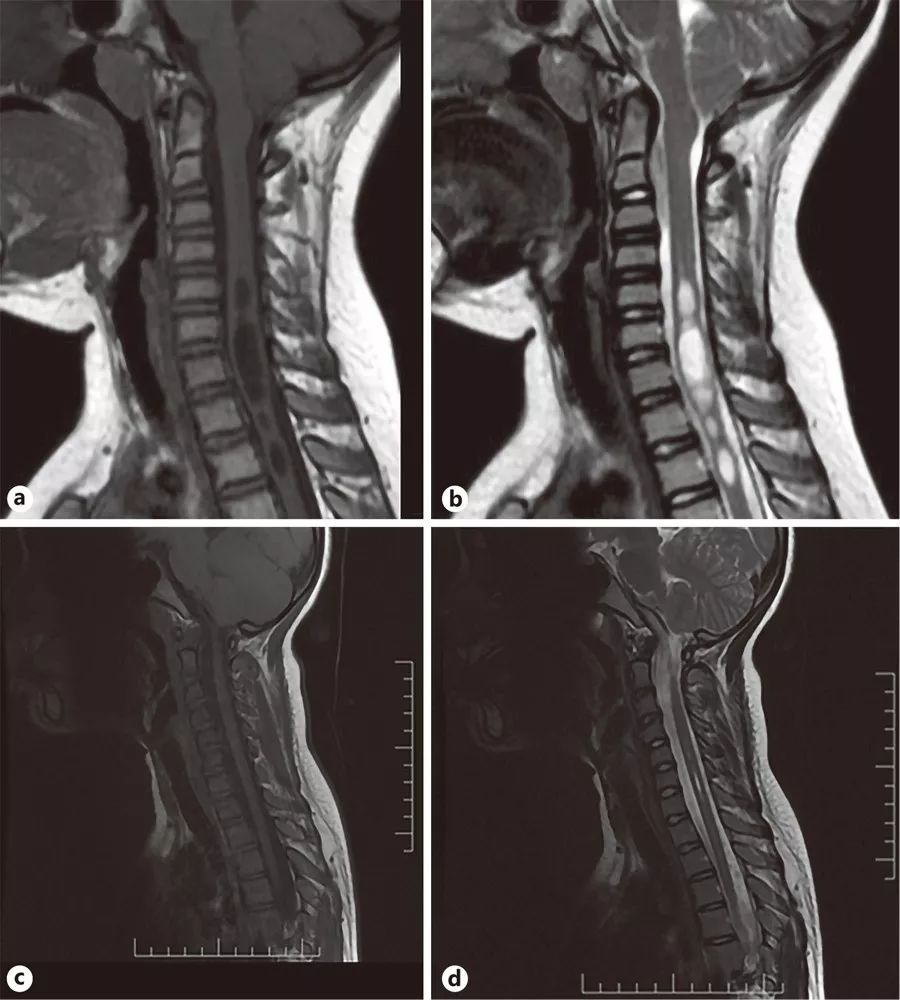

图2

患儿,女,9岁。在2010年首次做T1加权(A)和T2加权(B)MRI。在2017年首次做T1加权(C)和T2加权(D)MRI。到2017年,后脑疝几乎消失,脊髓空洞缩小。